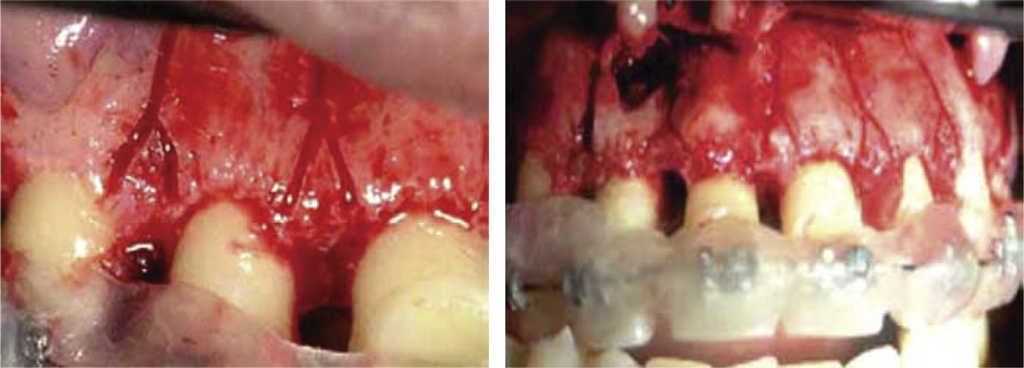

Modified corticotomy technique

Germec published an article in 2006 where he presented his modified corticotomy technique. This technique significantly reduced surgical procedure time; it is a mono-cortical technique eliciting no negative effect in periodontal tissues, preserving as well pulp vitality of treated teeth. One week before undertaking surgery, it is recommended to stabilize upper and lower arches with 0.016″ x 0.022″ stainless steel arches.15

The main indication to use this technique is in patients with difficult lingual or palatal surgical access. Its greatest advantage lies in elimination of palatal or lingual flaps, as well as cuts in the cortical bone at the site; this results in surgical time decrease and thus greater comfort and lesser stress for the patient.15

Infiltrative local anesthesia is used in this surgical technique; a mucoperiosteal flap is raised from a vestibular direction, under dental apexes. Vertical cuts must be achieved with a low speed, 0.5 mm diameter stainless steel round burr, from the gingival margin up to 2 or 3 mm underneath dental apexes, with a 1.5 to 2 mm depth on the cortical bone (Figure 12).15